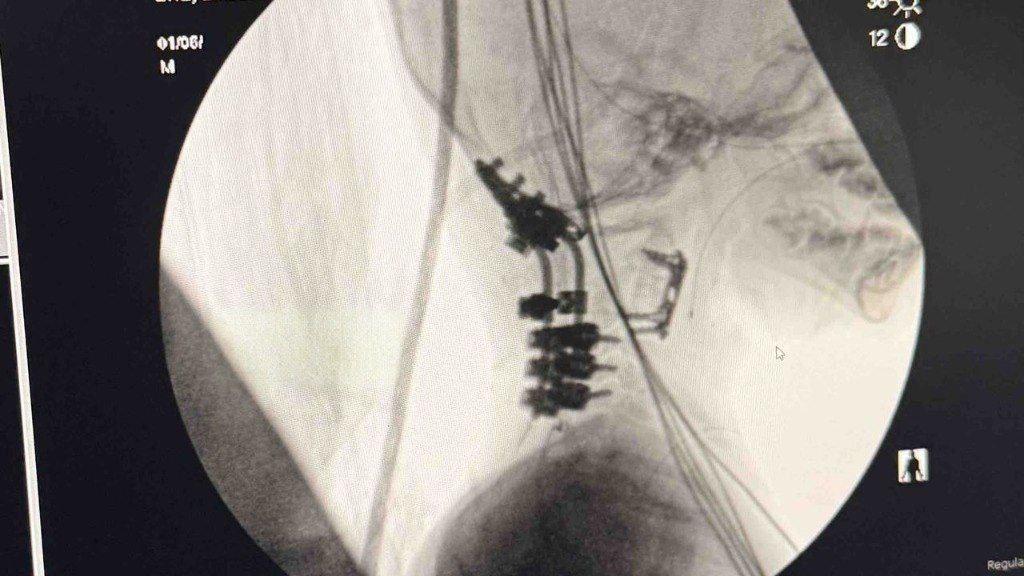

В результате лобового столкновения с грузовиком у ребёнка произошло полное отделение головы от позвоночника.

Врачи констатировали несовместимую с жизнью травму, но провели уникальную операцию по реконструкции спинного мозга и шейных позвонков.